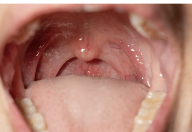

식도암 증상 원인 치료방법 등 식도암 관련 정보에 대해 알아보도록 하겠습니다.식도암은 식도 내부의 세포에서 암이 생기는 것을 의미합니다. 주로 알코올, 담배, 식습관 등이 원인이 될 수 있습니다. 초기에는 증상이 나타나지 않아 조기 발견이 어려우며, 증상이 나타나면 음식이 삼키기 어려운 협착감이나 통증 등이 나타날 수 있습니다. 진단을 위해 내시경 검사, 조직검사 등이 이루어지며, 수술, 방사선 치료, 항암화학요법 등이 치료 방법으로 사용될 수 있습니다. 조기 발견과 치료의 중요성이 강조되며, 건강한 식습관과 생활 습관을 유지하고 음주와 담배를 자제하는 것이 예방에 큰 도움이 됩니다.

식도암의 초기에는 증상이 나타나지 않을 수 있습니다. 그러나 암이 진행되면 다음과 같은 증상이 나타날 수 있습니다.

식도암은 조기 발견이 어려워 위험요인이 있거나 증상이 나타나면 즉시 전문가의 진단을 받아야 합니다. 만약 식도암이 의심된다면 내시경 검사, 조직검사 등을 통해 정확한 진단을 받아 치료를 시작하는 것이 중요합니다.